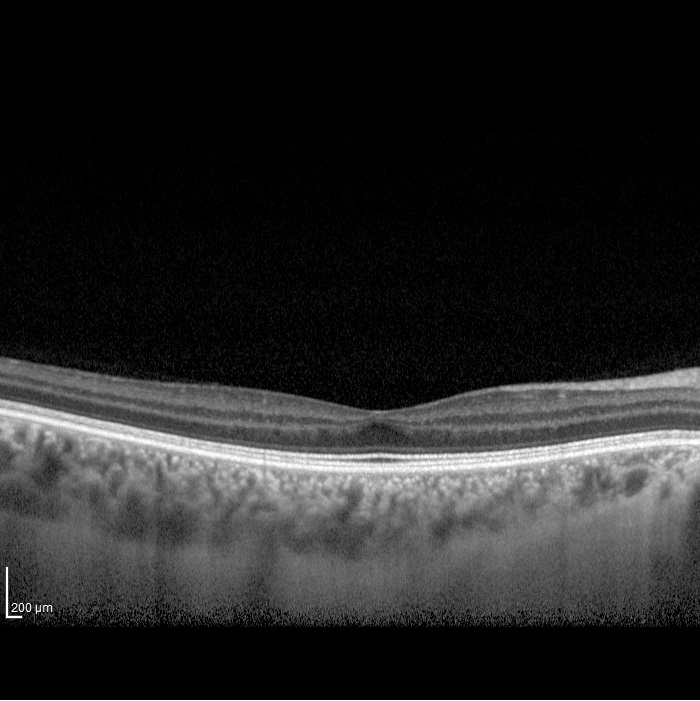

Three different patients with isolated grade 1 foveal hypoplasia. The definitions of fovea plana and foveal hypoplasia have led to controversy among experts. The term fovea plane refers to the anatomical absence of a foveal pit. An estimated 3% of children with clinically normal eyes have an underdeveloped foveal pit on OCT. According to some experts, a foveal pit is not absolutely necessary for foveal cone specialization. A diagnosis of fovea plana alone does not automatically herald functional disability. It is possible to maintain adequate visual acuity in an eye with a fovea plana. Foveal hypoplasia refers to an underdeveloped fovea with vision loss. Foveal hypoplasia has also been seen in conditions such as aniridia, albinism, achromatopsia, nanophthalmus, and incontinence. pigment and premature retinopathy.

Grade 1a foveal hypoplasia is associated with an almost normal pit resembling a “V” shape and outer segment (OS) elongation and outer nuclear layer (ONL) expansion relative to parafoveal OS and ONL lengths, respectively.

Grade 1b foveal hypoplasia is associated with a shallow indentation and OS prolongation and ONL widening relative to parafoveal OS and ONL lengths, respectively.